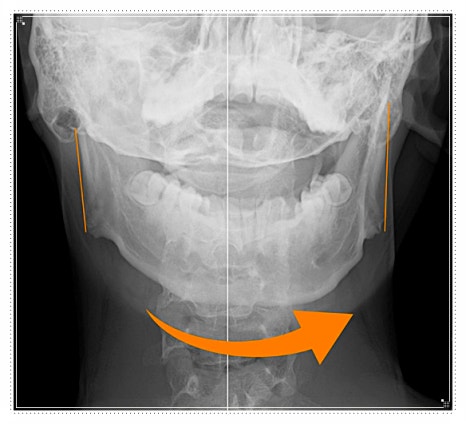

위아래 치아가 곧게 내려오나요, 아니면 한쪽으로 치우쳐 보이나요?

한쪽으로 쏠린다면 교합 균형이 흐트러졌다는 신호일 수 있습니다.

하지만 시간이 지나면 입 벌어짐이 더 줄고, 얼굴 비대칭이 눈에 띄며 턱뼈와 관절에 부담이 누적됩니다.